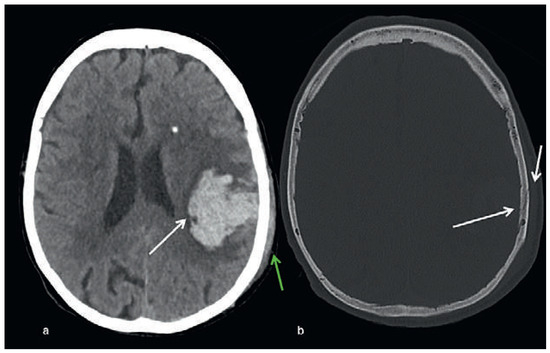

Head and brain trauma: general aspects and neuroimaging

by Johanna Maria Lieb, Christoph Stippich and Meritxell Garcia

Swiss Arch. Neurol. Psychiatry Psychother. 2015, 166(8), 279-292; https://doi.org/10.4414/sanp.2015.00374 - 1 Jan 2015

In this article the general clinical aspects, imaging indications and different injury mechanisms of traumatic brain injury (TBI) are reviewed. In addition, the different imaging modalities and strategies are presented, including more specific imaging features of the various injuries. Computed tomography (CT) is [...] Read more.

In this article the general clinical aspects, imaging indications and different injury mechanisms of traumatic brain injury (TBI) are reviewed. In addition, the different imaging modalities and strategies are presented, including more specific imaging features of the various injuries. Computed tomography (CT) is the imaging modality of choice in the acute phase owing to its wide availability and short scanning time, as well as to its high sensitivity for the detection of fractures and acute bleeding. Although magnetic resonance imaging (MRI) is superior to CT in many other aspects, it plays no role in the acute phase. MRI, however, has been proven to be useful and complementary to CT in the subacute and chronic stages as well as in the case of inconclusive results on initial CT. Especially the use of standard sequences like fluid attenuated inversion recovery (FLAIR), diffusion and susceptibility weighted imaging (DWI and SWI) have been shown to increase the diagnostic potency in diffuse axonal injury, in mild brain trauma and also in more chronic stages of TBI. The use of more advanced MRI techniques such as diffusion tensor imaging (DTI), magnetic resonance spectroscopy (MRS), functional MRI (fMRI) and magnetic transfer imaging (MTI) can further complete the diagnostic evaluation and give insights into different pathophysiological processes in TBI. Full article